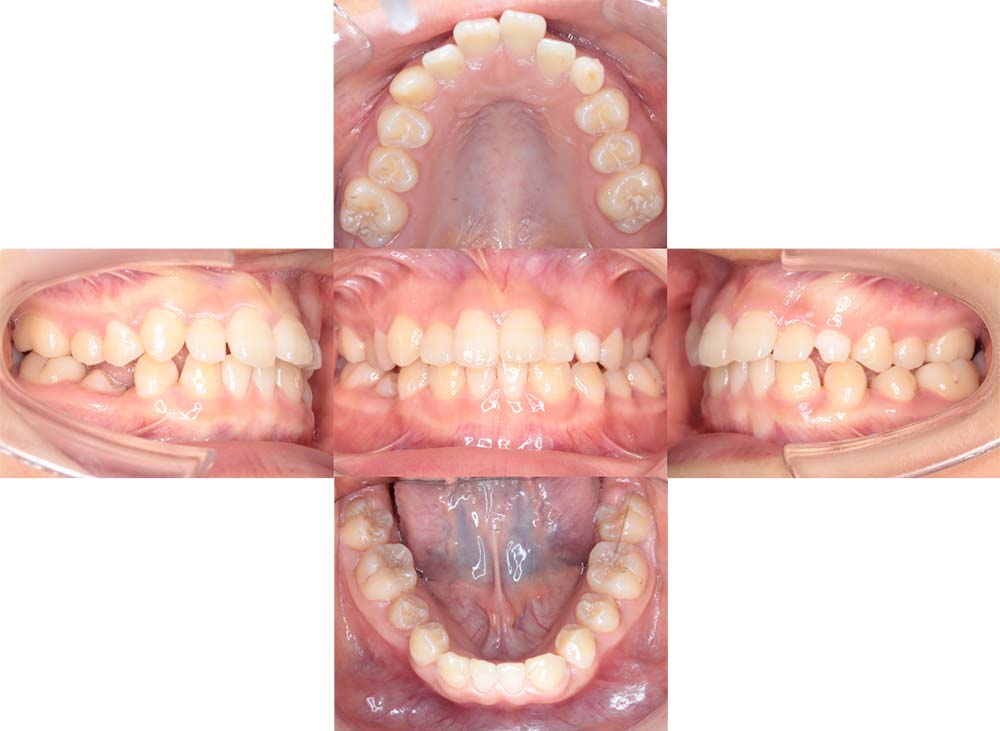

症例04

| 主訴 | 歯並びのガタガタと出っ歯が気になる。 |

| 診断名あるいは主な症状 | 上顎前突、叢生 |

| 年齢/性別 | 16歳・女性 |

| 矯正ステージ | 大人の矯正治療 |

| 治療方法 | ワイヤー矯正 |

| 抜歯部位/抜歯有無 | 抜歯 |

| 治療内容 | 抜歯したスペースを使用し、ガタガタの改善と上下顎前歯を後退させた。 |

| 費用 |

85万円程度(2025.10時点の料金となります。) ※矯正基本料金、審美ブラケットを含む |

| 治療期間 | 2年5ヶ月 |

| 主なリスク・副作用 | 痛み、歯根吸収、歯肉退縮、虫歯、後戻り |